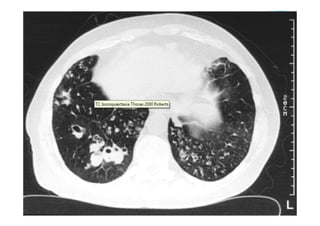

Radiografia e TC de tórax

Utiliza-se com frequênciap/ avaliar: O posicionamento do TOT: 4-6 cm acima da carina; Se os pulmões estão sendo aerados adequadamente; Alterações patológicas e diagnóstico de pneumopatias; Outros. Radiografia e TC de tórax